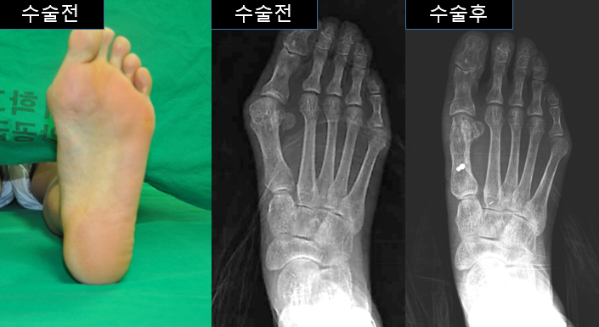

그림 1. 무지외반증의 수술 전 및 수술 후의 모습 |